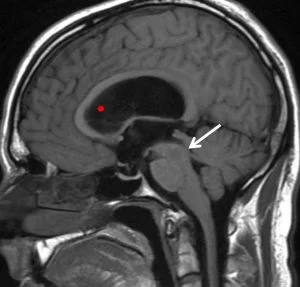

Ο υδροκέφαλος φυσιολογικής πίεσης (Normal Pressure Hydrocephalus – NPH) αναφέρεται σε μια κατάσταση στην οποία οι κοιλίες του εγκεφάλου έχουν αυξημένο μέγεθος, όμως η πίεση του εγκεφαλονωτιαίου υγρού είναι φυσιολογική. Ο NPH είναι επικοινωνών υδροκέφαλος, δηλαδή δεν υπάρχει απόφραξη σε κάποιο σημείο του κοιλιακού συστήματος και διαφοροποιείται από τον αποφρακτικό ή μη επικοινωνούντα υδροκέφαλο, στον οποίο υπάρχει απόφραξη της κυκλοφορίας του εγκεφαλονωτιαίου υγρού (CSF) στο κοιλιακό σύστημα (π.χ. στένωση του υδραγωγού του Sylvius).

Ο υδροκέφαλος διακρίνεται επίσης σε επικοινωνών ή μή-επικοινωνών (αποφρακτικός). Στον επικοινωνώντα υδροκέφαλο δεν υπάρχει σε κάποιο σημείο του κοιλιακού συστήματος απόφραξη, δηλαδή το εγκεφαλονωτιαίο υγρό μπορεί να κυκλοφορεί ελεύθερα αλλά δεν απορροφάται σωστά. Ο μη-επικοινωνώντας υδροκεφαλός – που ονομάζεται επίσης “αποφρακτικός” υδροκέφαλος – συμβαίνει όταν η ροή του εγκεφαλονωτιαίου υγρόύ φράσσεται κατά μήκος μίας ή περισσοτέρων από τις στενές διόδους που συνδέουν τις κοιλίες. Μία από τις πιο συχνές αιτίες υδροκεφάλου είναι η στένωση του υδραγωγού. Στην περίπτωση αυτή, ο υδροκέφαλος οφείλεται σε στένωση του υδραγωγού του Sylvius, ένα μικρό πέρασμα μεταξύ της τρίτης και της τέταρτης κοιλίας στο κέντρο του εγκεφάλου.

Ο υδροκέφαλος εκ κενού εμφανίζεται όταν υπάρχει καταστροφή εγκεφαλικής ουσίας όπως π.χ μετά απο ένα εγκεφαλικό επεισόδιο ή τραύμα. Σε αυτές τις περιπτώσεις, ο εγκέφαλος μπορεί να συρρικνωθεί, γεγονός που με τη σειρά του οδηγεί σε αύξηση του κοιλιακού συστήματος. Ο υδροκέφαλος φυσιολογικής πίεσης (NPH) είναι μια ανώμαλη αύξηση του εγκεφαλονωτιαίου υγρού στις κοιλίες του εγκεφάλου που μπορεί να προκύψει από μια υποαραχνοειδή αιμορραγία, τραύμα της κεφαλής, λοίμωξη, όγκο ή επιπλοκές χειρουργικής επέμβασης. Ωστόσο, πολλοί άνθρωποι αναπτύσσουν NPH χωρίς κανέναν από αυτούς τους παράγοντες.

Οι αιτίες του υδροκεφάλου δεν είναι ακόμη καλά κατανοητές. Ο υδροκέφαλος μπορεί να προκύψει από κληρονομικές γενετικές ανωμαλίες (όπως το γενετικό ελάττωμα που προκαλεί στένωση του υδραγωγού) ή αναπτυξιακές διαταραχές (όπως αυτές που σχετίζονται με προβλήματα σύγκλεισης του νευρικού σωλήνα, συμπεριλαμβανομένης της δισχιδούς ράχης και της εγκεφαλοκήλης). Άλλες πιθανές αιτίες περιλαμβάνουν επιπλοκές του πρόωρου τοκετού όπως η ενδοκοιλιακή αιμορραγία, ασθένειες όπως μηνιγγίτιδα, όγκοι, εγκεφαλικό τραύμα ή η υποαραχνοειδής αιμορραγία, οι οποίες εμποδίζουν την έξοδο του εγκεφαλονωτιαίου υγρού από τις κοιλίες στις δεξαμενές ή προκαλούν προβλήματα απορρόφησης του ΕΝΥ.